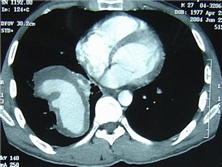

神经白塞综合征是指既有神经系统损伤的白塞综合征,又称神经白塞病。除口腔粘膜阿弗他...